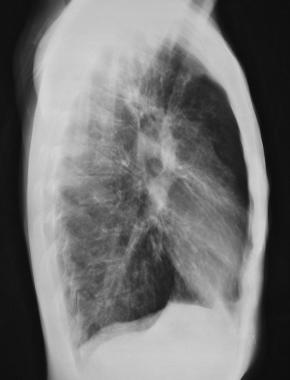

图2 侧位胸片显示胸骨后间隙增大(充气过多)